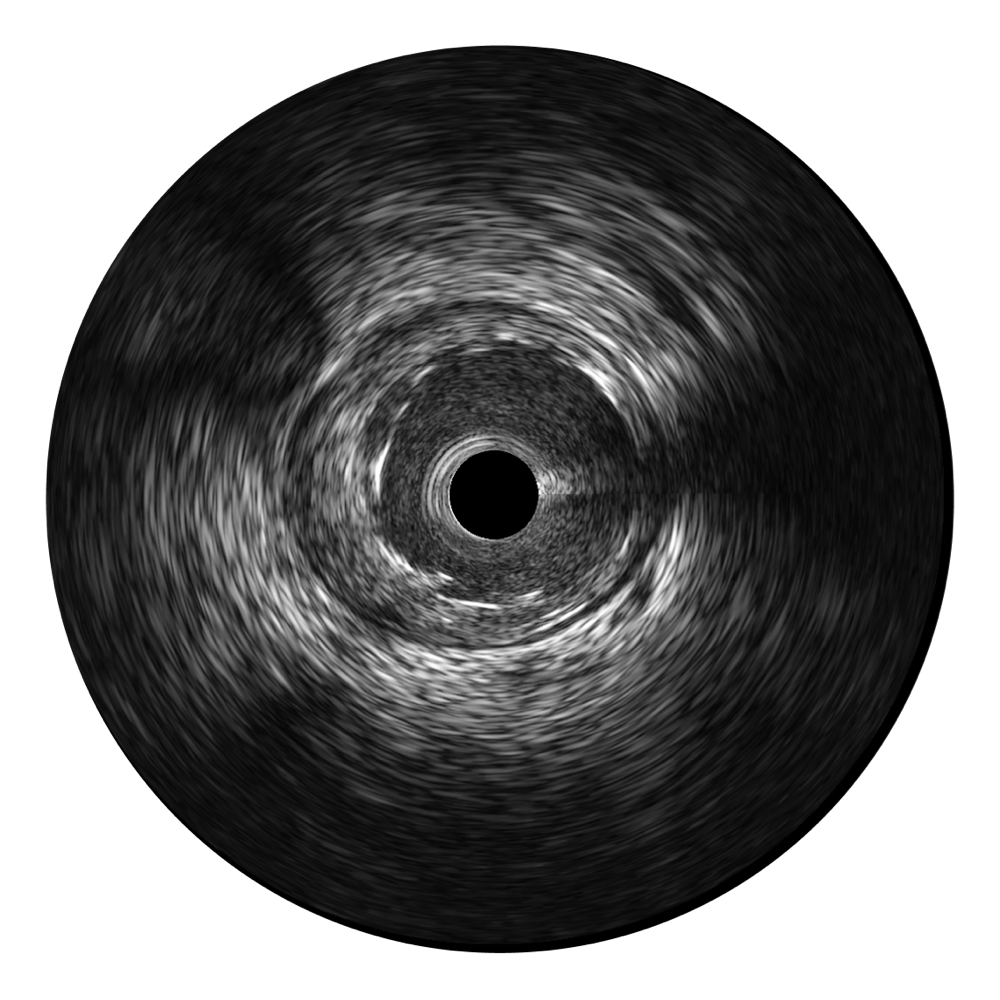

乐玩lewin国际宽频IVUS图像

传统IVUS图像

对比传统IVUS导管成像,乐玩lewin国际宽频IVUS图像的近场支架梁显影更细腻,远场中膜外血管仍清晰可辨,兼顾远中近,兼顾分辨力与穿透深度